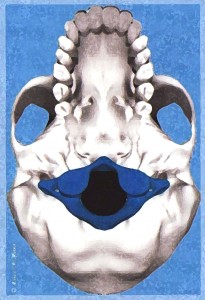

Az öreglyuk melletti bütykök elhelyezedése nem szimmetrikus, deformálódtak az idegek, erek csontos kijáratai és maga az öreglyuk is. Megdöbbentő bizonyítékot találtunk az atlasz koponyaalpot torzító elfordulására. Egy idős ember koponyáját alaposan megvizsgálva a következő tudományos bizonyítékot leltük: Az elfordult atlasz torzította és csontos átépülésre késztette a koponyaalap fontos alkotórészeit: az atlasszal ízesülő bütyköket, a koponyaalapról kilépő csontos csatornákat, […]]]>

Az öreglyuk melletti bütykök elhelyezedése nem szimmetrikus, deformálódtak az idegek, erek csontos kijáratai és maga az öreglyuk is. Megdöbbentő bizonyítékot találtunk az atlasz koponyaalpot torzító elfordulására. Egy idős ember koponyáját alaposan megvizsgálva a következő tudományos bizonyítékot leltük: Az elfordult atlasz torzította és csontos átépülésre késztette a koponyaalap fontos alkotórészeit: az atlasszal ízesülő bütyköket, a koponyaalapról kilépő csontos csatornákat, […]]]>